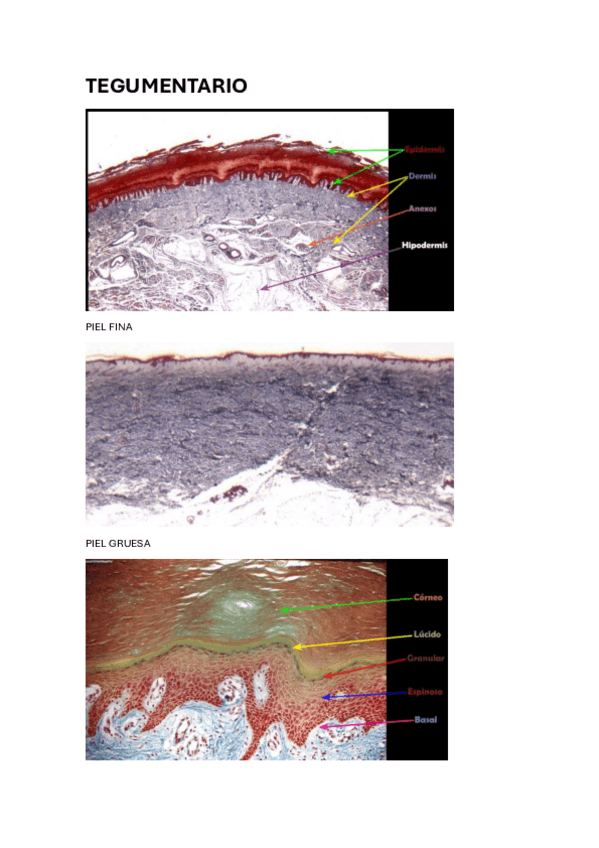

PRÁCTICAS HISTOLOGIA

Todas las practicas de histologia resueltas y con imágenes

He publicado nuevos examenes de 1º Histología Médica: CUESTIONARIO-TEGUMENTARIO.pdf

5 páginas

He publicado nuevos apuntes de 1º Histología Médica: HISTOLOGIA-T1-TEGUMENTARIO.pdf

7 páginas

He publicado nuevos apuntes de 1º Histología Médica: SISTEMA-TEGUMENTARIO.pdf

26 páginas